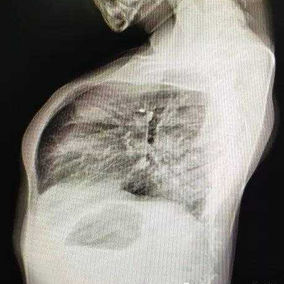

The patient was a 4-year-old boy who has been suffering from physical deformities since birth, manifested as a protrusion of the anterior chest wall and the disappearance of the physiological curvature of the spine. Initially, the deformities were mild and did not cause any discomfort, so the patient did not receive treatment. However, starting at the age of 3, the chest wall deformity became more pronounced and significantly altered the appearance of his chest wall.

The patient exhibits a noticeable protrusion of the chest wall and a loss of normal spinal curvature, resulting in a visibly unbalanced appearance. He was eventually diagnosed with flatback syndrome combined with a convex deformity of the chest wall.

First, incisions were made on both sides of the chest wall. The Wenlin procedure was then performed to correct the protrusion on the chest wall. Due to a secondary concavity near the xiphoid process, an incision was made at the xiphoid process to perform the standard Wang procedure for correcting this newly developed deformity. The surgery was completed in 1 hour, successfully correcting the malformations and restoring the chest wall to a normal appearance.